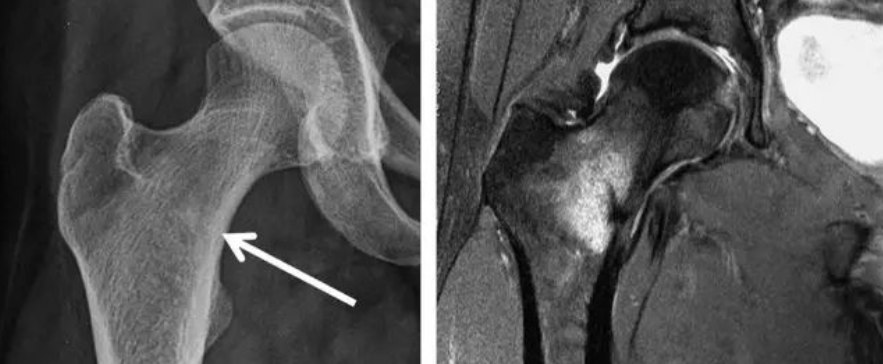

股骨头坏死的治疗效果与病情轻重、发现早晚、病程长短有很大关系,病变发现越早,病情越轻,治疗效果越好。